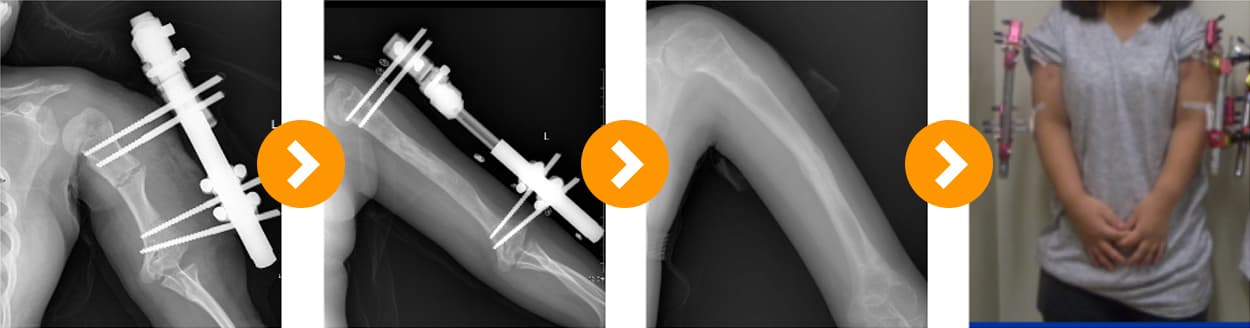

연골 무형성증상지 연장술 10cm